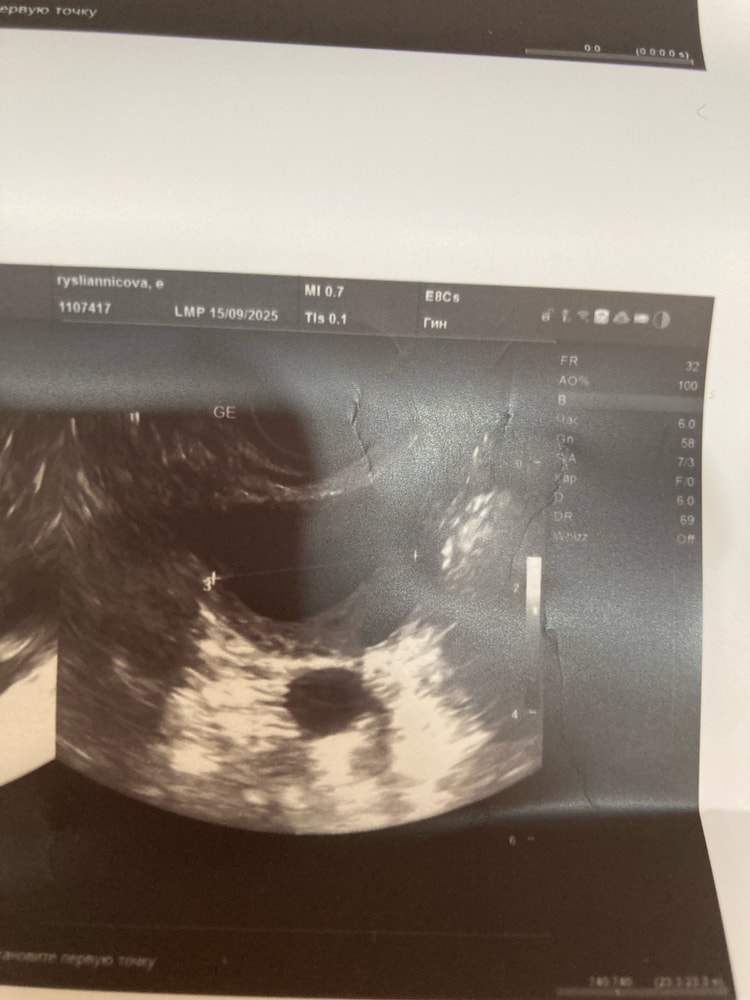

На 17дц: фолликул в левом 20мм, эндометрий 6,9мм, шейка раскрыта на 1,7мм с жидкостью 👀

Сегодня на 20дц: фолликул вымахал до 26мм, эндометрий до 10, шейка до 2,1мм раскрылась так же с жидкостью

Эндометрий был трехслойный, стал гипоэхогенный прости господи